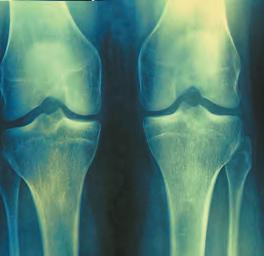

1. For each of the photographic examples A-C above, classify the data as quantitative, ranked, or qualitative:

(a) Skin color:

A: Skin color